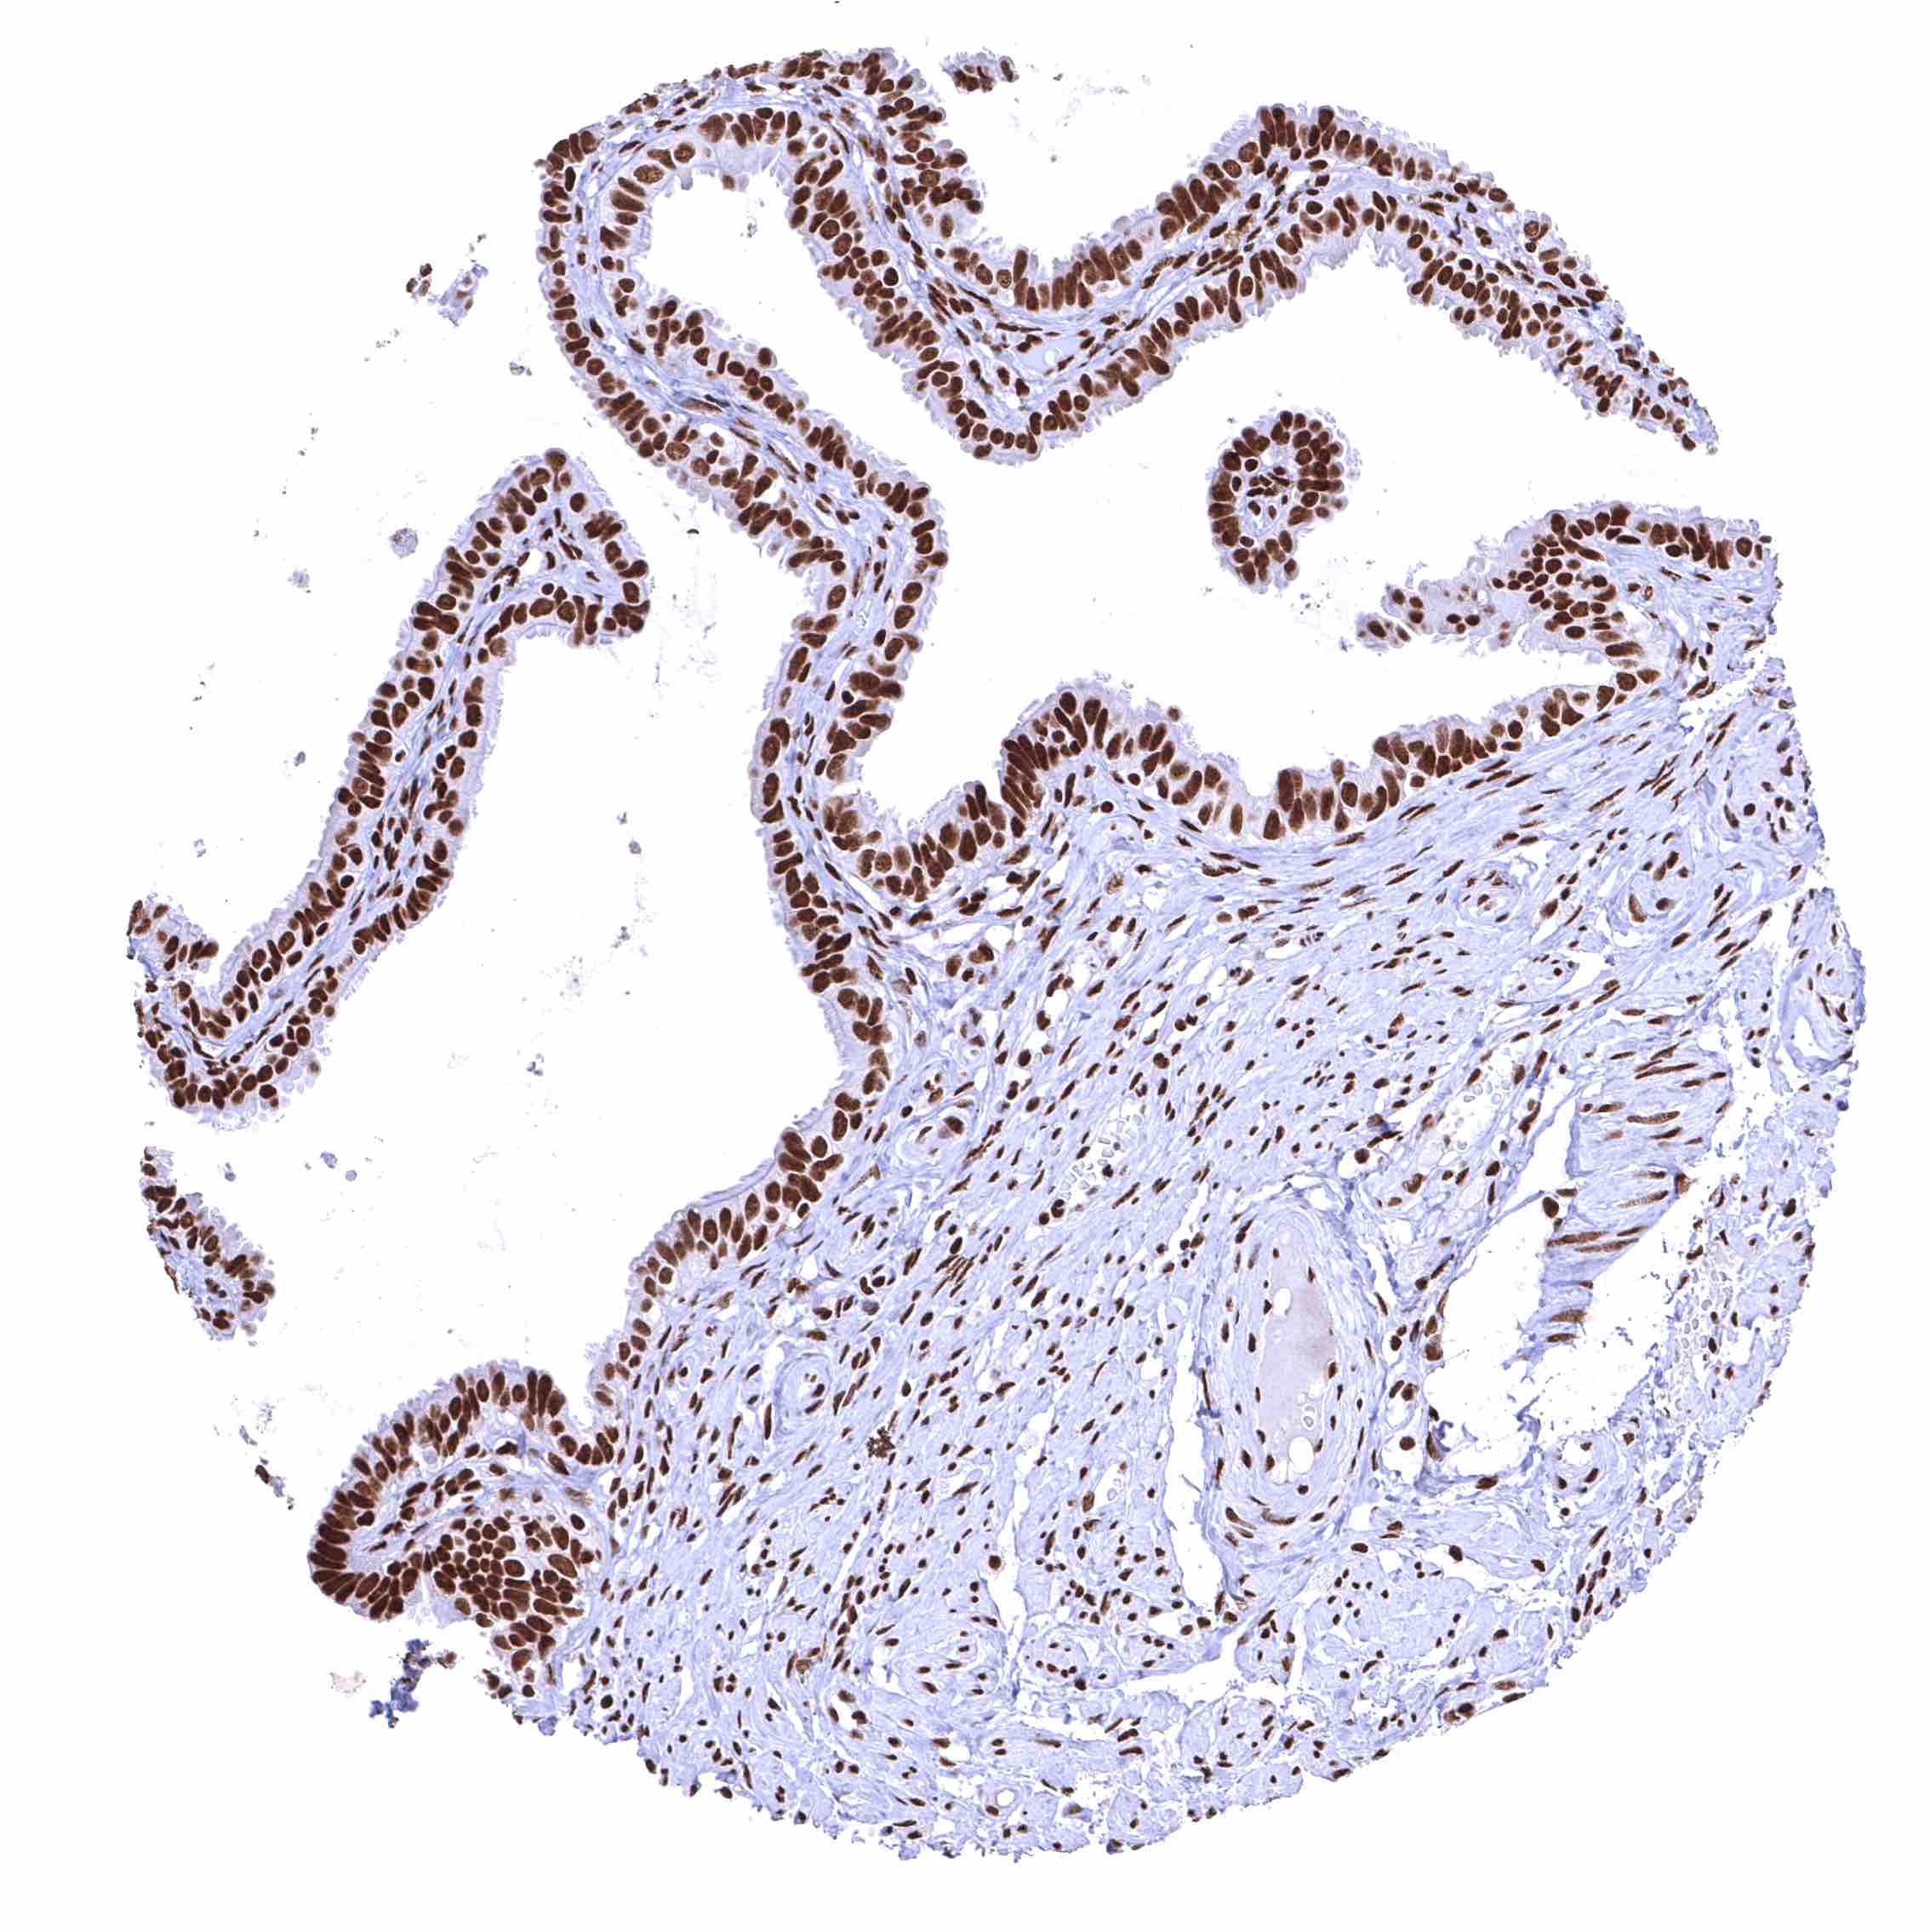

BRD4 antibody [HMV4275] HistoMAX™

Fallopian tube, mucosa – Strong nuclear BRD4 staining of epithelial cells.